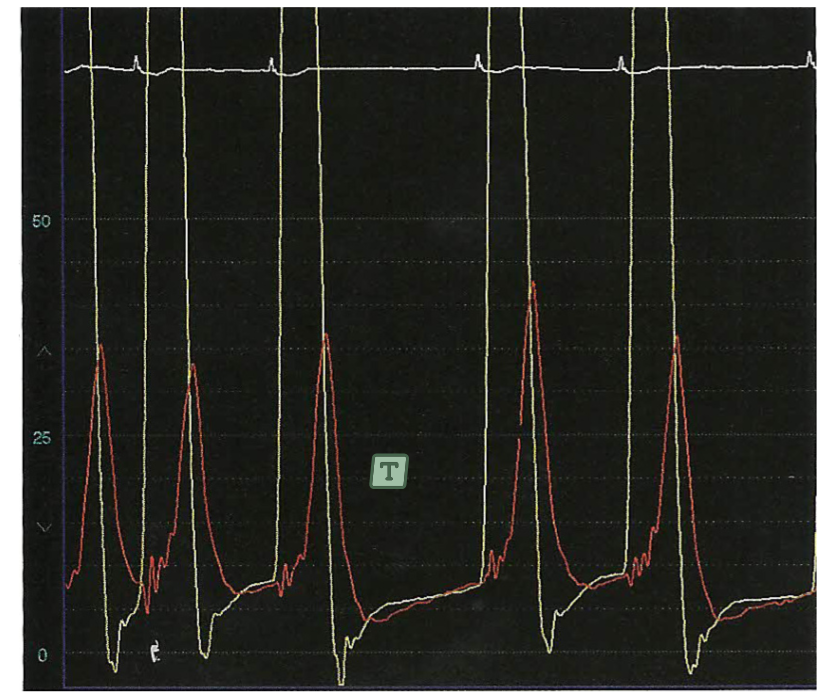

Como calculo o índice de regurgitação aórtica após a TAVI ? a pessoa me dá os gráficos

Índice de Reg aórtica = (PDAo = PD2Ve)/ PS x 100 Resultado é 28 ( menor que 28 seria leve) --> 28 mostra ausência

59

QUal é o PD2 do VE aqui ?

10 mmHg.